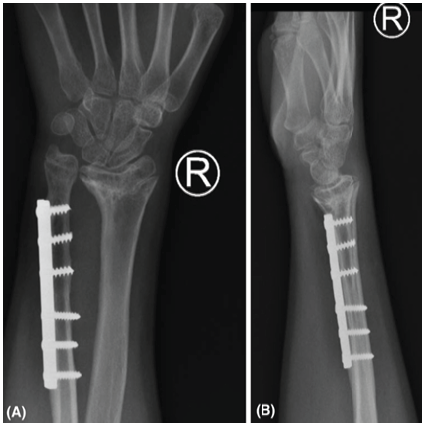

In-terms of patient-related outcome, the patient and his parents were extremely satisfied with the surgical outcome in terms of increased functional ROM and cosmetic appearance of the hand and wrist. After these satisfactory results and outcomes, the patient and his parents were asked to proceed with operative treatment for the right wrist. At 7 years and 6 months post-injury, he underwent the exact same surgical intervention for the right side under general anesthesia. The ulnar shortening was almost 1.9 cm to aligned distal radioulnar joint. The boy had an uneventful post-operative course, and he was evaluated at 2 and 8 weeks post-surgical intervention, as same as previous post-operative course then to be followed by 2, 4, and 8 months consecutively. At 4 months post-operative, clinical evaluation demonstrated improved ROM, including supination/pronation, with pain-free wrist (Fig. 4 and Table 1). The radiographs showed adequate union of the osteotomy site with an ulnar neutral wrist in aligned position (Fig. 5). In-terms of patient-related outcome, the patient and his family were satisfied with the results. At the time of reporting the case, the patient is 6 months post-surgical intervention for the right side with an improving range of motion, and he is currently following with physiotherapy along with our pediatric orthopedic clinic.

Figure 5: (a): Final right wrist anteroposterior X-ray. (b) Final right wrist lateral X-ray.